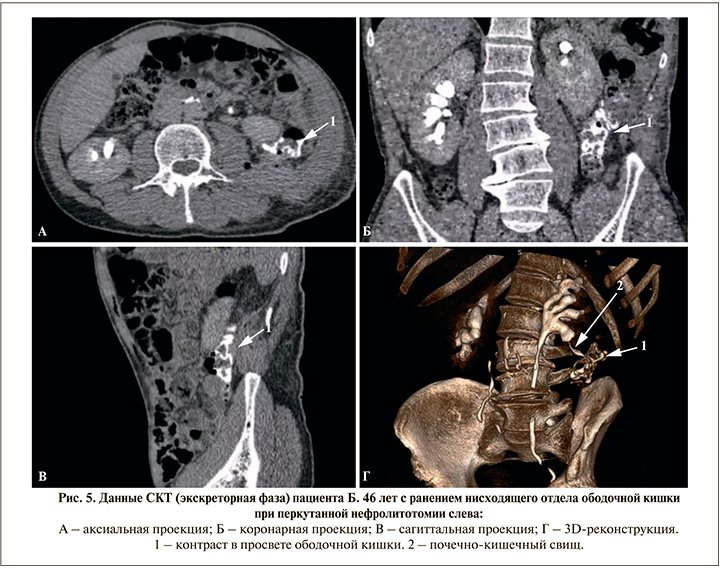

С целью диагностики травмы ободочной кишки во время чрескожной нефролитотомии многие авторы рекомендуют СКТ в нативном режиме и с экскреторной фазой, которая может быть дополнена при необходимости антеградной уретеропиелографией (фистулографией) или ретроградной уретеропиелографией.

Перед планируемой выпиской на 3-и сутки пациент предъявил жалобы на интенсивную пневматурию. Отсутствовали лихорадка и лейкоцитоз, парез кишечника и перитонеальные симптомы. Выполненная в экстренном порядке сонография не выявила признаков уростаза и жидкостных образований паранефрально на стороне операции, также отсутствовала свободная жидкость в брюшной полости. Однако при проведении СКТ с болюсным контрастированием выявлены скопления газа в верхних мочевыводящих путях слева и мочевом пузыре (рис. 4), в экскреторную фазу визуализировался свищевой ход и поступление контраста в ободочную кишку (рис. 5). Таким образом, была верифицирована травма ободочной кишки с наличием внутреннего толстокишечно-почечного свища. Кишечное отделяемое или моча в области перкутанного доступа, как и признаки локального воспаления, отсутствовали (рис. 3b).